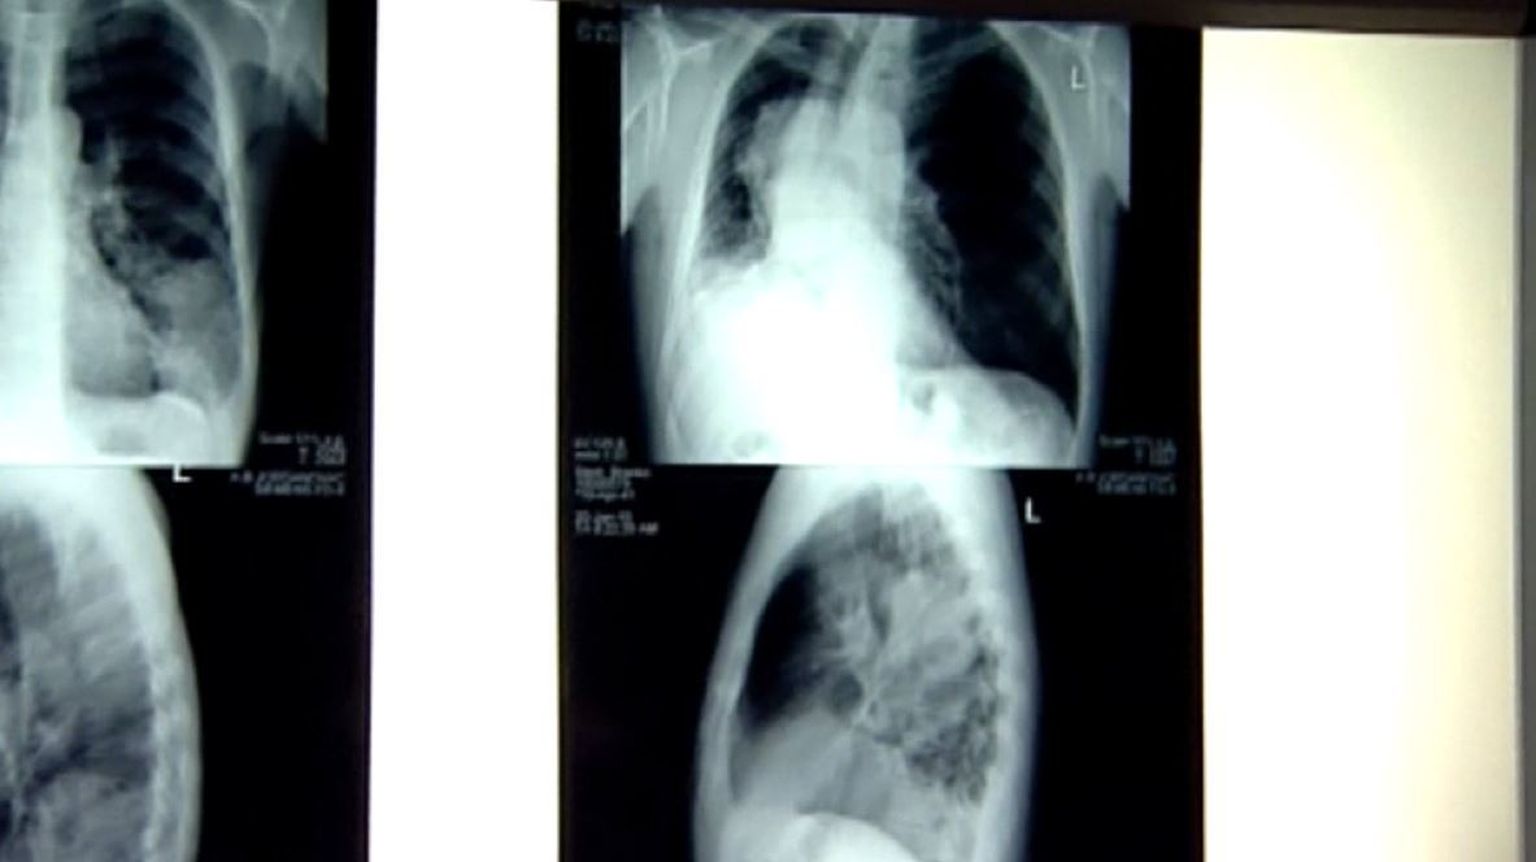

• Borba protiv raka (Foto: Dnevnik.hr) - 1 Foto: DNEVNIK.hr

• Borba protiv raka (Foto: Dnevnik.hr) - 4 Foto: DNEVNIK.hr

• Borba protiv raka (Foto: Dnevnik.hr) - 3 Foto: DNEVNIK.hr

• Borba protiv raka (Foto: Dnevnik.hr) - 2 Foto: DNEVNIK.hr

• Borba protiv raka (Foto: Dnevnik.hr) - 5 Foto: DNEVNIK.hr